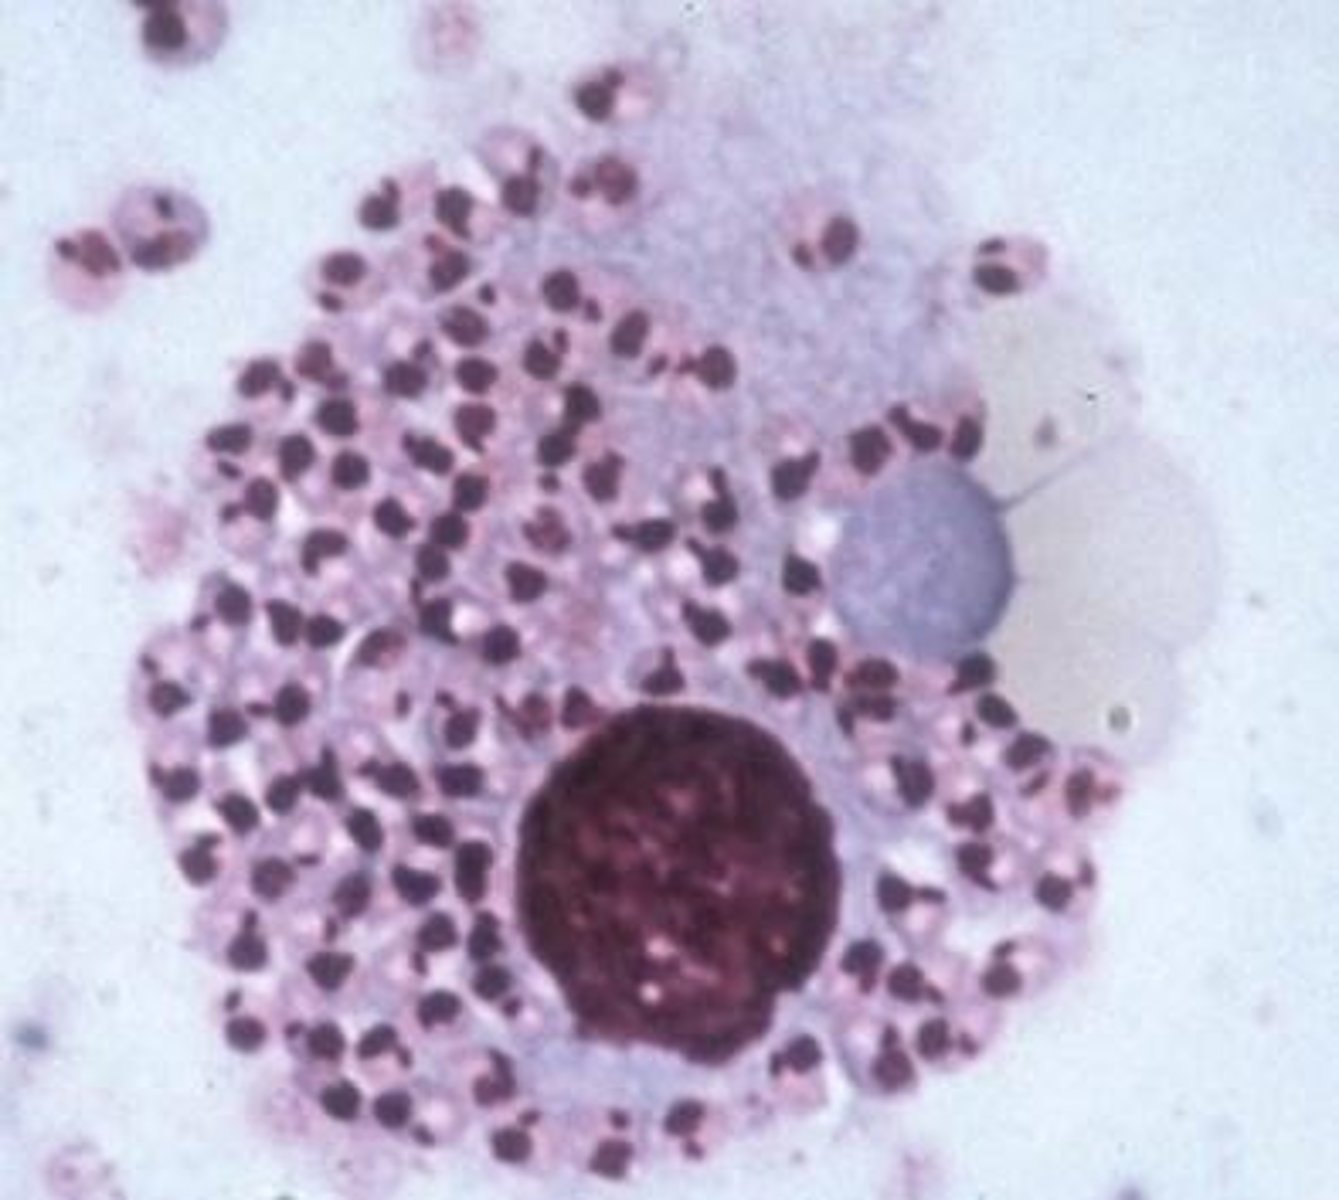

Leishmania infantum

ID the following parasite as a nest within a macrophage (dog)